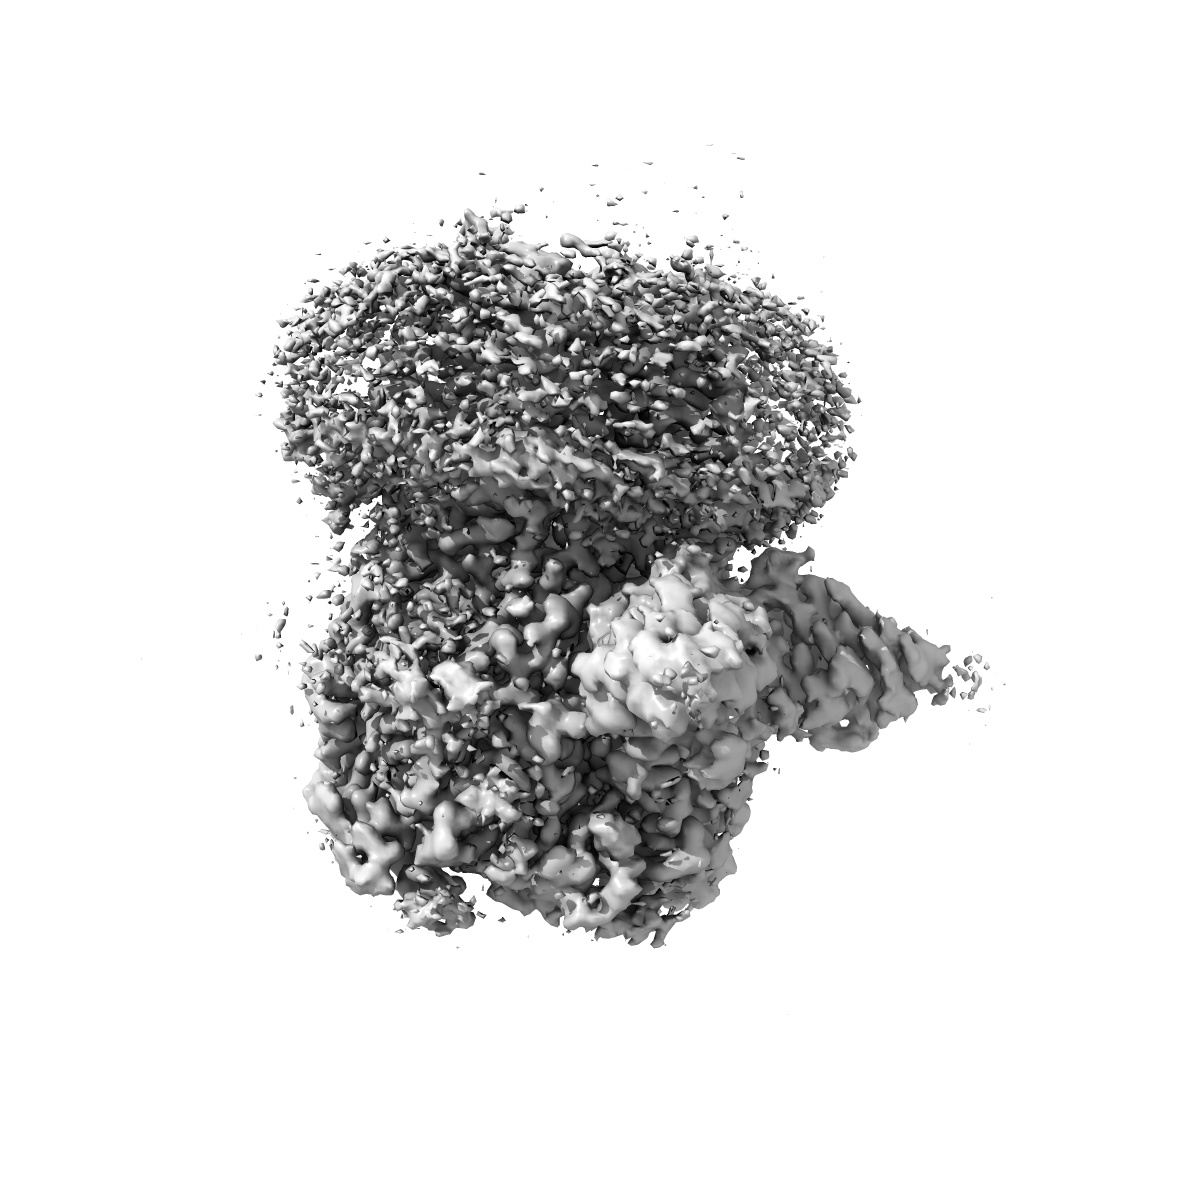

Cryo-EM structure of human full-length extrasynaptic alpha4beta3delta GABA(A)R in complex with nanobody Nb25

Single-particle2.5 Å

Sample: Human full-length extrasynaptic alpha4beta3delta GABA(A)R in complex with Nanobody Nb25